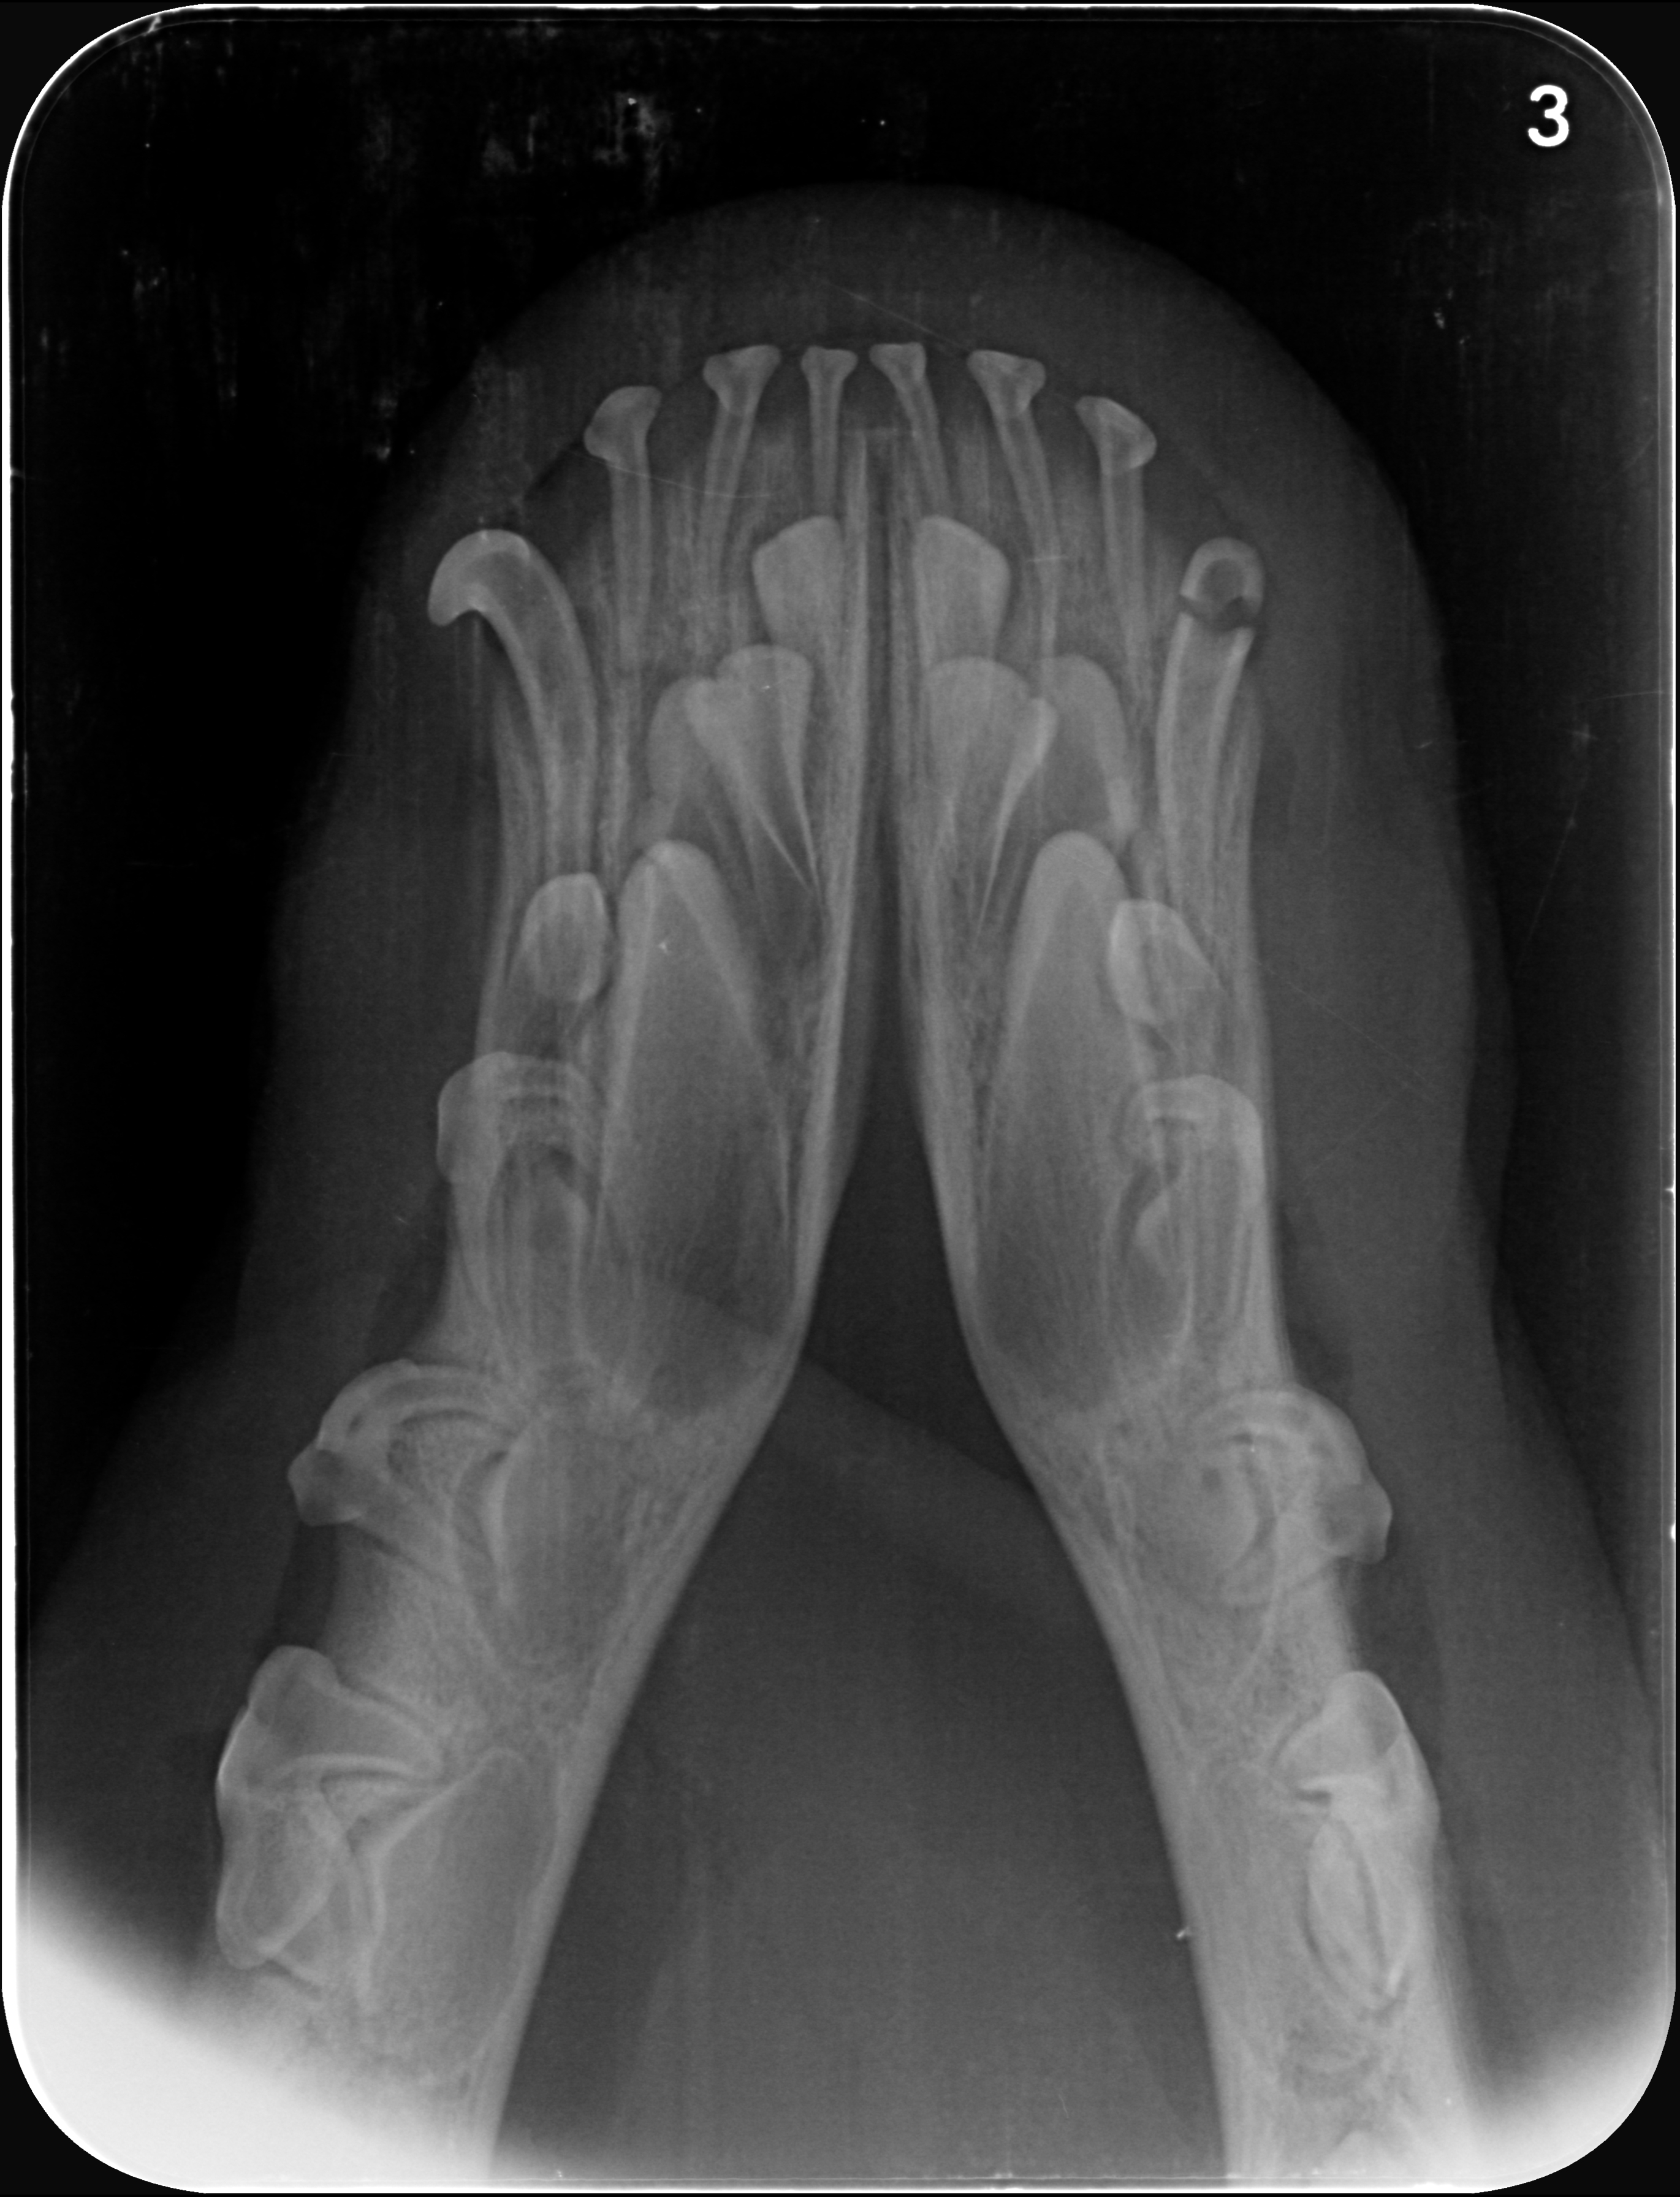

Nous pouvons également effectuer le dépistage de maladies génétiques, vectorielles ou virales, quand votre animal a pu y être exposé, notamment par des tests rapides sanguins, des tests génétiques ou encore des examens radiographiques lorsqu'ils sont indiqués.